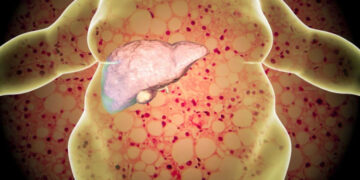

Read moreহার্টবিট ডেস্ক শরীরের গুরুত্বপূর্ণ এক অঙ্গ হলো লিভার। শরীর সুস্থ রাখতে এই বিশেষ অঙ্গ নানা ধরনের কাজ করে থাকে। যেমন-শরীরে...